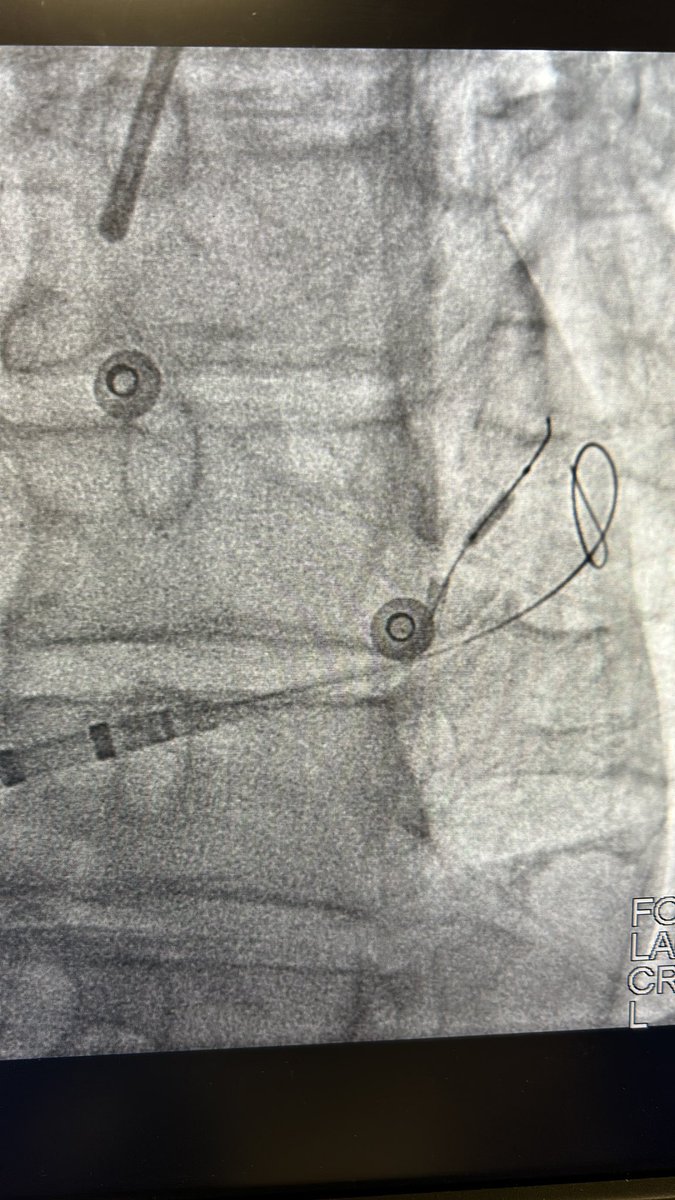

More evidence mounting that lines of block during baseline rhythm are indeed fixed isthmus boundaries for VT. 👏🏻@Davilandre @BidmcCvi

pubmed.ncbi.nlm.nih.gov/38819346/ VT ablation without the need for VT induction and the use of activation map to better understand the substrate.